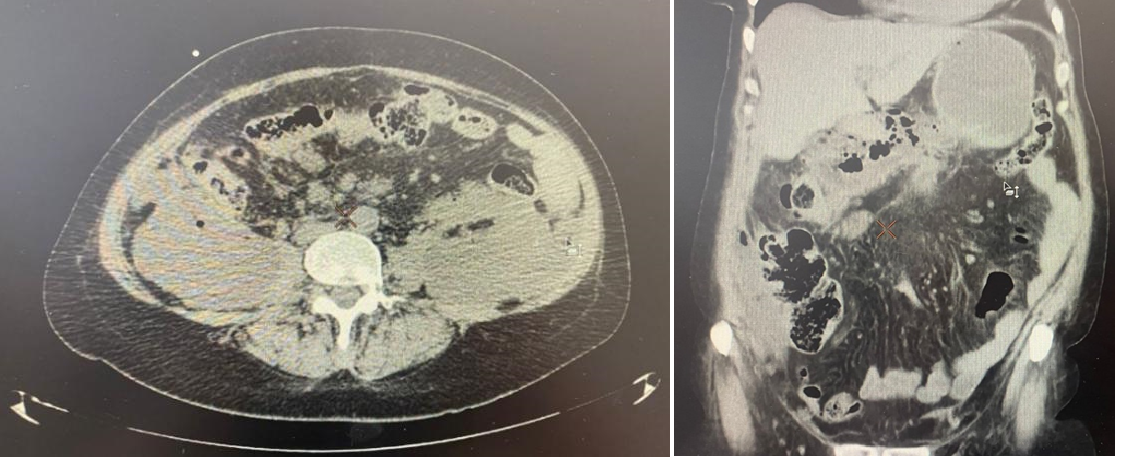

Контрольное обследование на третьи сутки. Повторный лабораторный контроль выявил следующие показатели: лейкоциты 14,1×10⁹/л, амилаза 187 U/L, фибриноген 2,8 г/л, АЧТВ 32,4 сек. Повторное исследование тромбодинамики показало изменение параметров: Cs — 14 мкм, Vi — 59,3 мкм/мин. Данные компьютерной томографии поджелудочной железы свидетельствовали о сохраняющемся увеличении её объёма, снижении плотности паренхимы, а также о наличии отёка и инфильтративных изменений в парапанкреатической клетчатке.

Рисунок 2 - Пример компьютерной томографии течения острого панкреатита